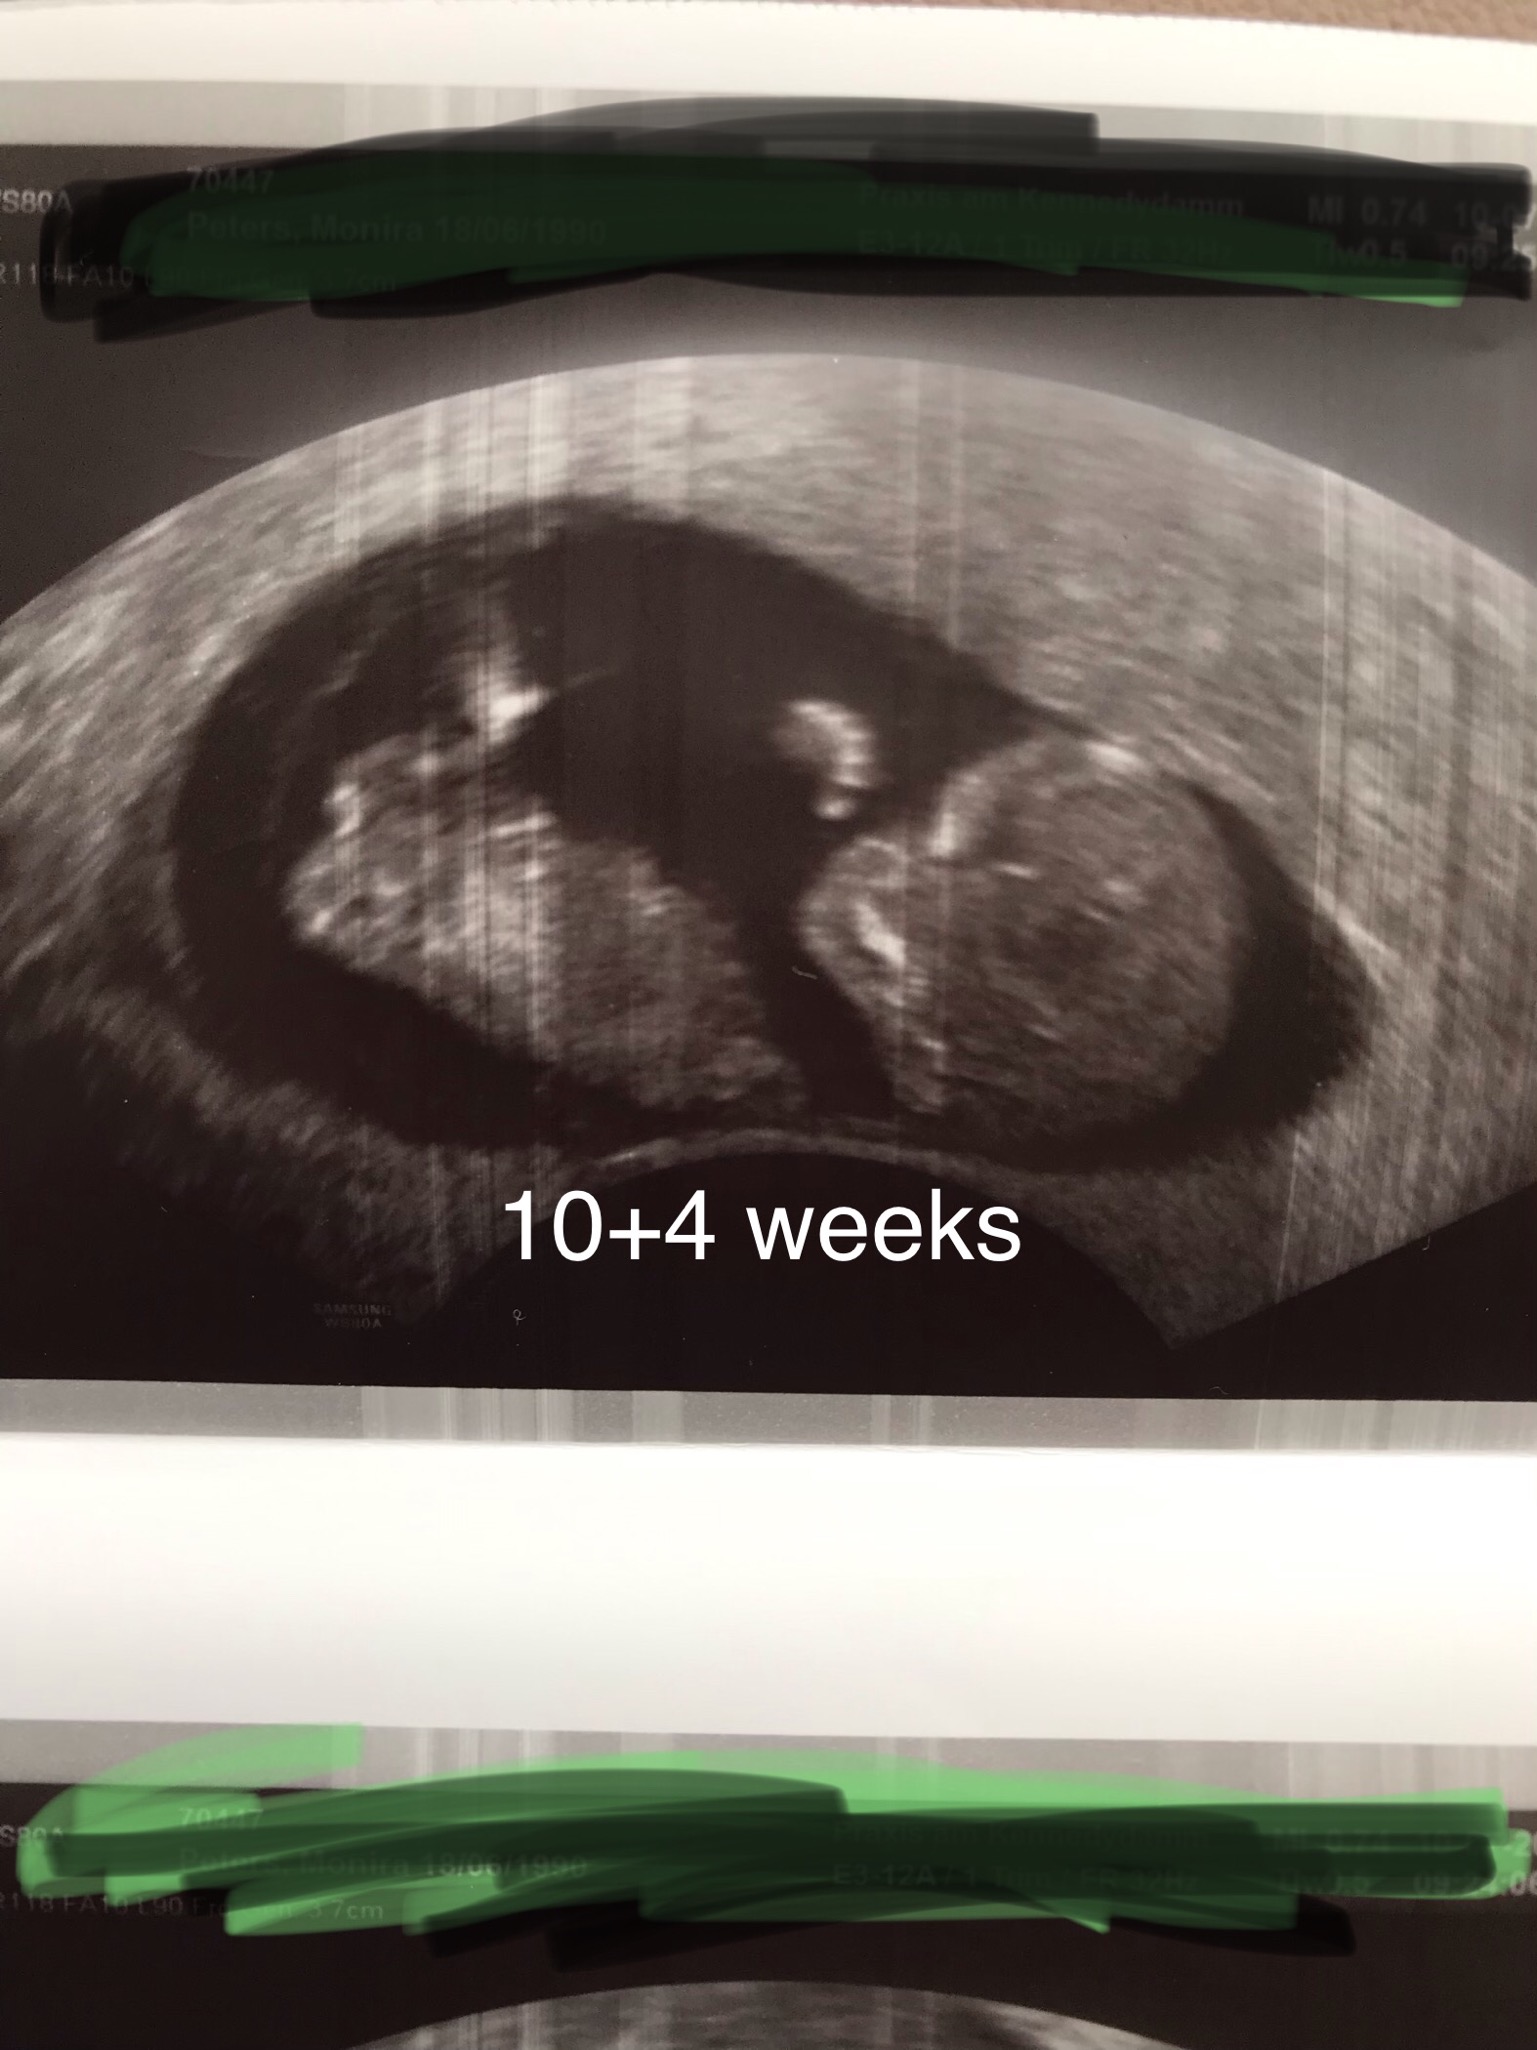

Attachment 41755Attachment 41756

I can't guess this early, but sending you tons of pink dust!

Hoping its pink - will u be finding out later in preg?

Too early, even for fun